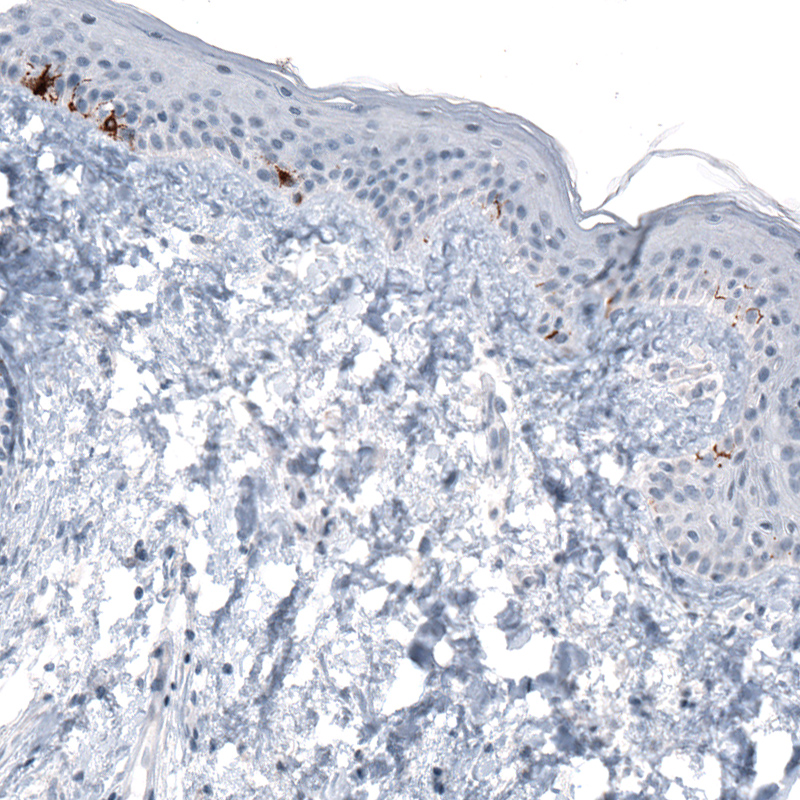

Immunohistochemical staining of human skin shows strong cytoplasmic immunoreactivity in melanocytes.